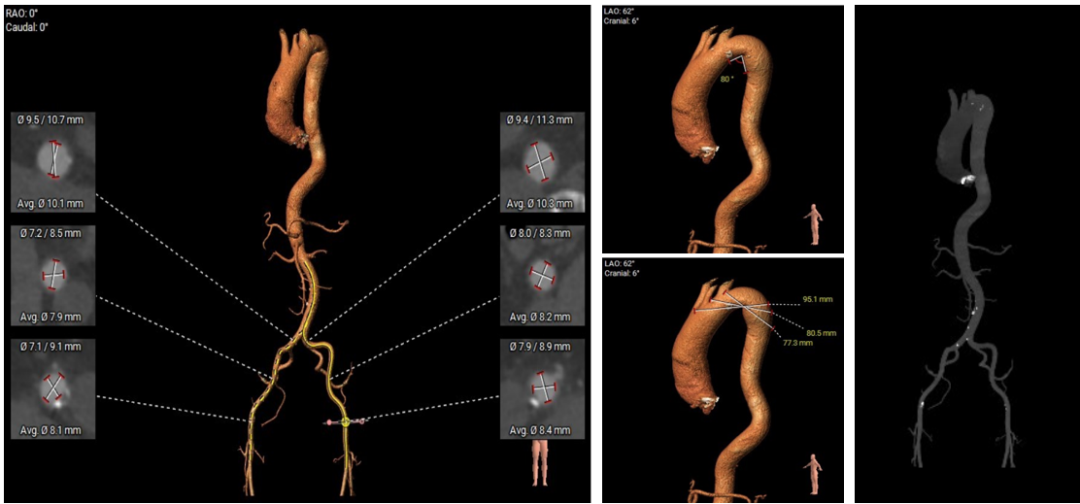

●瓣环平面与水平夹角为64°,横位心,主动脉弓夹角、弓距尚可;

●入路血管情况良好。

●横位心,主动脉弓夹角、弓距尚可,升主动脉扩张,输送器能过弓、跨瓣难度增加,备Snare辅助。